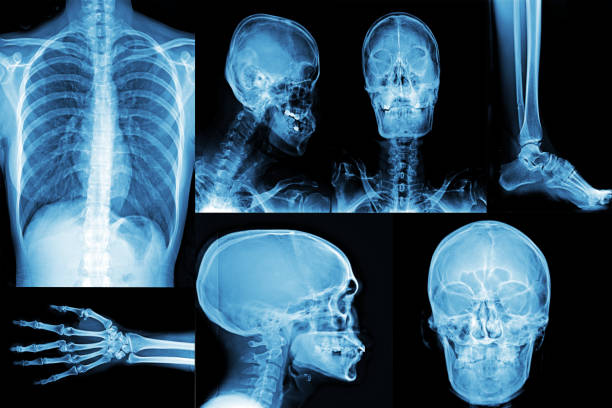

Digital X-Ray

Digital X-rays are an advanced form of medical imaging that uses digital sensors instead of traditional photographic film to produce and store images of the body’s internal structures. This technology offers several significant advantages over traditional X-rays, including higher image quality, lower radiation exposure, and faster results.